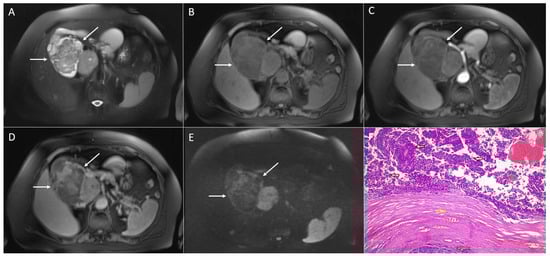

4. Solid Pseudopapillary Neoplasm Mimicking Cystic Pancreatic Lesions

4.3. Walled-Off Necrosis